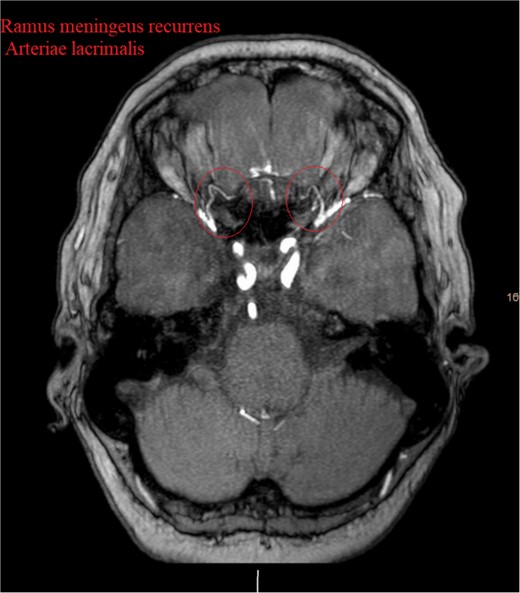

Brain CT imaging unveiled a hypodense fronto-basal lesion measuring 9–10 cm with finger-shaped perifocal edema (Fig. 1). contrast-enhanced cMRI provided more precise dimensions of the lesion (52 x 41 x 82 mm), demonstrating mild compression on both lateral ventricles and posterior displacement of the right middle cerebral artery and both anterior cerebral arteries without signs of hydrocephalus or perfusion disturbances (Fig. 1) and the bilateral COF anastomoses (Fig. 2) .

Show the MRA with the bilateral anastomotic branch of the lacrimal artery with the middle meningeal artery.

In our case, a notable feature was the circular anastomosis among arterial branches, reminiscent of the unique Hyrtl anastomosis [5]. This configuration resembled the meningeolacrimal variant of the Ramus lacrimalis originating from the middle meningeal artery, traversing the Hyrtl canal (HC) [1]. The HC, positioned variably lateral to the superior orbital fissure, is linked to the persistence of an embryonic canal for the supraorbital division of the stapedial artery, forming a canal for bilateral anastomosis between the orbital branch of the middle meningeal artery and the lacrimal branch of the ophthalmic artery in 26% of cases [1]. This finding offers a unique perspective on the vascular considerations associated with our case’s meningioma blood supply.